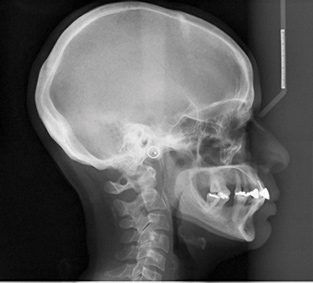

Fig 1. A prominent symphysis was present as seen in lateral cephalometric image.

Figure 1